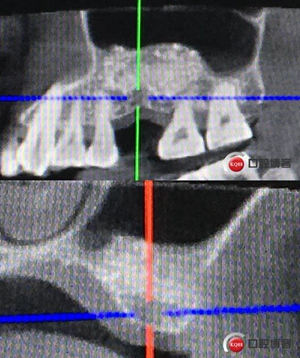

患者女性,58歲,身體健康,無不良咀嚼習慣,不吸煙、不飲酒。兩年前因左上后牙反復咬合痛,嚴重影響進食就診,檢查發(fā)現(xiàn)26號牙根尖周炎癥明顯,周圍骨吸收嚴重。拔除患牙,徹底掻刮,由于骨缺損嚴重,沒能即刻種植。6個月后來門診種植。

骨高度僅有3mm,寬度充足。計劃外提升,根據(jù)骨質(zhì)情況決定是否同期植入植體,切開翻瓣,暴露上頜竇頰側(cè)骨壁。

骨高度比曲斷片顯示的更低,不利于同期植入,直接縫合。

術(shù)后X光片,植骨量充足。

術(shù)后8個月,X光顯示骨量充足,密度明顯增加。